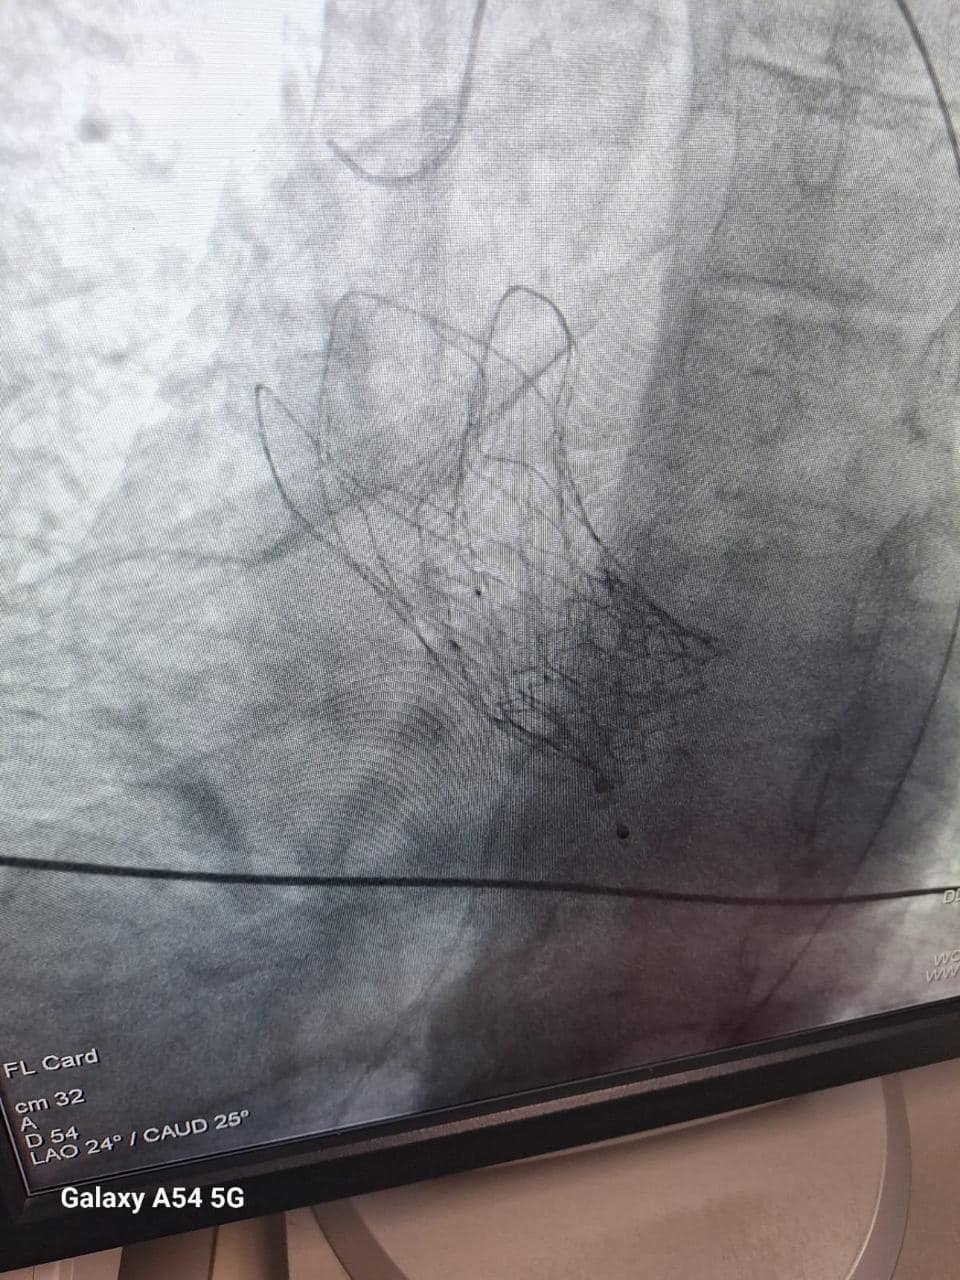

Transcatheter aortic valve implantation (TAVI)

Introduction: Transcatheter aortic valve implantation (TAVI) has revolutionized the management of aortic stenosis, offering a less invasive option for patients deemed high-risk or inoperable for traditional surgical aortic valve replacement....